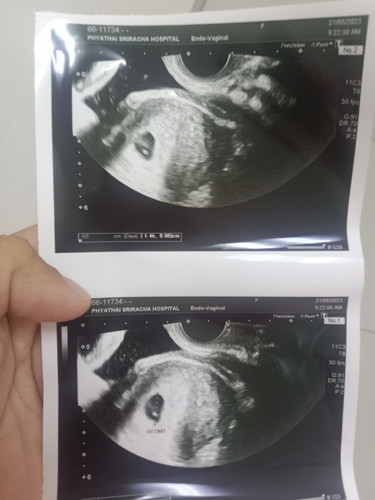

อัลตร้าซาวด์คลื่นหัวใจน้อง

อยากทราบว่าน้องยังอยู่ไหมค่ะ มีโอกาสท้องลมไหมค่ะแบบนี้ ขอปรึกษาแม่ๆหน่อยค่ะ ท้องได้ประมาณ6w